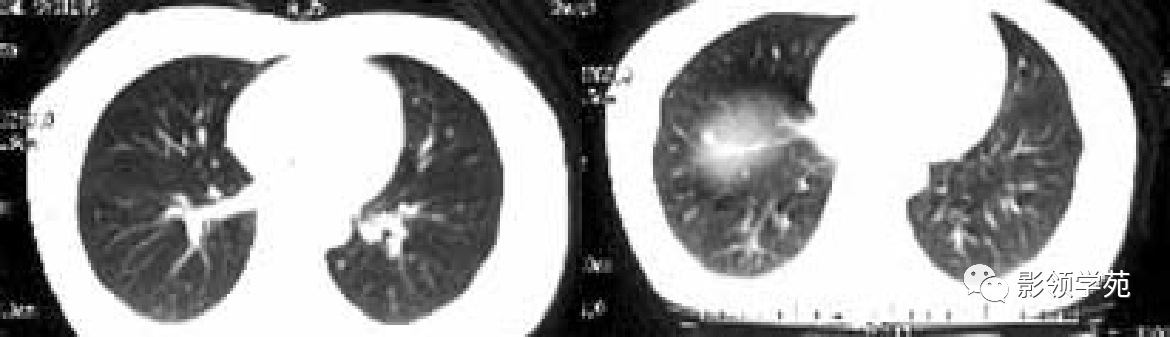

多发或单发结节,大小不一,边缘较清楚。少数结节伴出血时出现晕轮征,即有略高密度影像环绕结节,使病变边缘模糊。病变有钙化常见于骨肉瘤或软骨肉瘤转移。转移瘤亦可表现为空洞。两肺多发的小结节影具有随机分布的特点,HRCT显示结节位于小叶中心、小叶间隔、支气管血管束及胸膜,结节大小不均匀。

HRCT表现为沿淋巴管分布的结节。支气管血管束结节状增粗,并有结节,小叶间隔呈串珠状改变或增粗,小叶中心有结节灶,并有胸膜下结节。病变在两肺弥漫分布或局限于某一部位,以中下肺多见。常合并胸腔积液。约半数病人有纵隔及肺门淋巴结肿大。